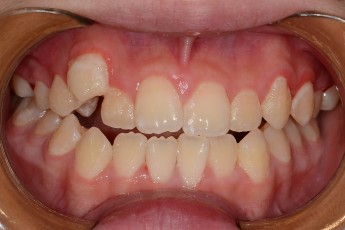

- 덧니교정

Before

After